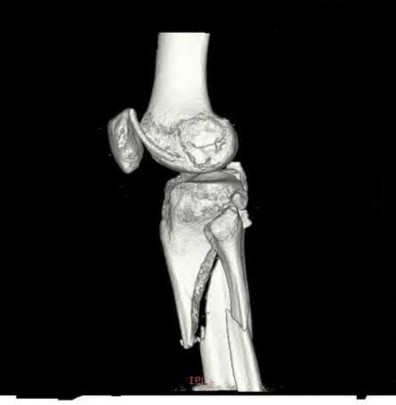

Which of the following will most likely result with the use of a fracture table when treating the injury shown in Figures A and B?

1) Internal malrotation deformity

2) External malrotation deformity

3) Recurvatum deformity

4) Varus deformity

5) Valgus deformity

The fracture table has been shown to induce an internal malrotation deformity when it is used for treating femoral shaft fractures.

Intramedullary nailing with reaming of the bone and static locking of the nail is the treatment of choice for femoral shaft fractures in adults. The fracture table has been used with excellent results. Compared to manual traction, the fracture table provides an advantage as only one assistant is necessary.

However, it may limit access to the patient if other body areas are injured. Additionally, the fracture table has been shown to induce an internal malrotation deformity, which results from internally rotating the limb to facilitate access to the starting point and to improve visualization of the hip in the lateral plane. Rotation may also be difficult to assess clinically once the limb is positioned and draped.

Stephen et al. performed a randomized study comparing the fracture table and manual traction when nailing femoral shaft fractures. They found that internal malrotation was significantly more common when the fracture table was used. Operative time was also greater for the fracture table group. There were no other differences in complications. They concluded that manual traction is an effective technique that decreases operative time and improves the quality of reduction.

Figures A and B are AP radiographs demonstrating a femoral shaft fracture. Incorrect Answers:

Answers 2, 3, 4, & 5: Internal malrotation has been shown to be a risk when

using a fracture table to treat femoral shaft fractures by intramedullary nailing.